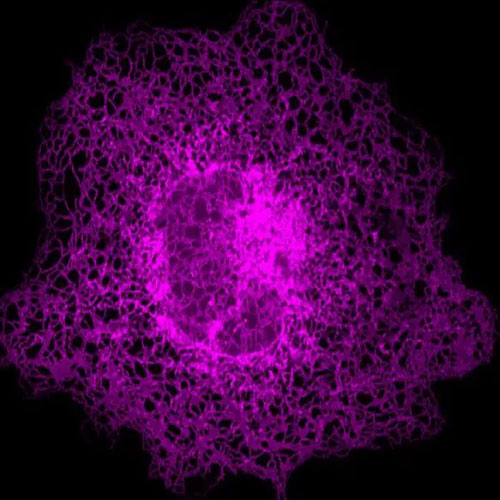

由于內質網是細胞中十分復雜且龐大的動態網絡,其形態和分布非常復雜。據了解,目前科學界沒有很好的方法實現精確定量分析內質網的拓撲結構和運動狀態。劍橋無限極研究中心研究人員通過3年的技術攻關,終于在此領域取得了突破性進展,將人工智能和超高分辨率成像系統結合建立了一套全新的智能分析體系“ERnet”,第一次實現了對活細胞內質網結構的精確定量分析。憑借在技術和科學認識上的顯著創新性,該成果發表在全球科學頂刊、生化研究方法領域排名第一的權威刊物《Nature Methods》(IF47.99)。

本研究則是CIRCE在細胞器和成像研究方面另一重大突破,本次研究重點對象為細胞內質網。“ERnet”基于Transformer的結構搭建而成,是全球現有最先進的機器學習骨干結構,被應用于多款其他人工智能模型中,如ChatGPT即是基于此擴展搭建而成。這個超分辨率成像技術與人工智能的融合給生物學研究帶來了革命性的影響,借助“ERnet”,研究人員發現了一種新的內質網結構——片上管狀內質網,這一發現首次證明了片狀和管狀內質網在結構上有廣泛的交集,更新了科學界對內質網結構、分布和動態的認識,后續能更深入了解其結構與功能紊亂的關系,在科學上具有重要的創新意義。